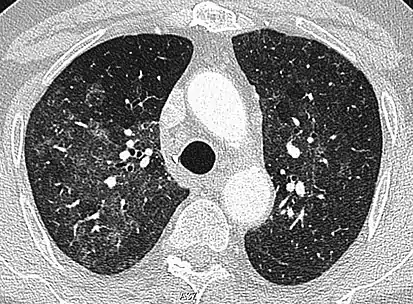

Ground-glass opacity is among the most common imaging findings in patients with confirmed COVID-19.[16][17] One systematic review found that among patients with COVID-19 and abnormal lung findings on CT, greater than 80% had GGOs, with greater than 50% having mixed GGOs and consolidation.[16] GGOs with mixed consolidation has most often been found in elderly populations.[18] Several studies have described a pattern among initial, intermediate, and hospital discharge imaging findings in the disease course of COVID-19. Most commonly, initial CT imaging reveals bilateral GGOs at the periphery of the lungs. During initial stages, this is most often found in the lower lobes, although involvement of the upper lobes and right middle lobe has also been reported early in the disease course.[16][18] This is in contrast to the two similar coronaviruses, SARS and MERS, which more commonly involve only one lung on initial imaging.[19][20] As the COVID-19 infection progresses, GGOs typically become more diffuse and often progress to consolidation.[11][18] This is sometimes accompanied by the development of a crazy paving pattern and interlobular septal thickening.[18] In many cases the most severe pulmonary CT abnormalities occurred within 2 weeks after symptoms began.[17] At this point, many individuals begin showing resolution of consolidation and GGOs as symptoms improve. However, some patients have worsening symptoms and imaging findings, with further increase in septal thickening, GGOs, and consolidation. These patients may develop lung "white-out" with progression to acute respiratory distress syndrome (ARDS) requiring treatment escalation.[17][21]